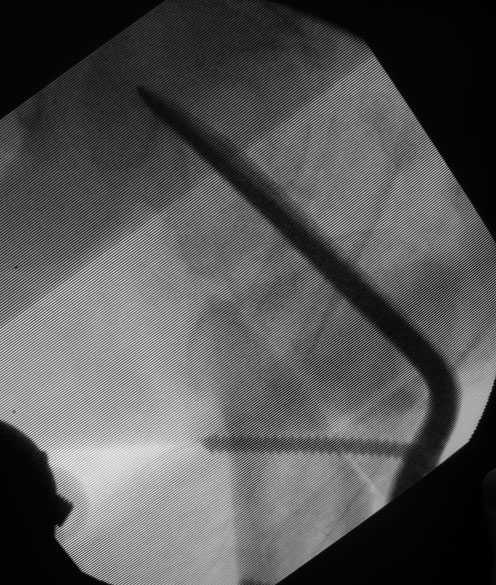

ОК, в центре ( ну уж никак не в наиболее нижнем сегменте :) головки и в верхней части шейки ( честно говоря, у меня складывается ощущение, лезвие входит в шейку либо сверху, а не через перелом, либо по верхнему кортикалу, но настаивать не буду - разрешение снимков недостаточно, чтоб говорить об этом с уверенностью)